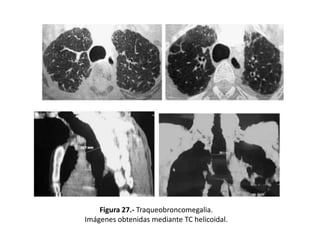

– Traqueobroncomegalia (S. de Mounier-Kuhn):

• Dilatación marcada de la tráquea y los bronquios principales

– BQ, fibrosis o enfisema.

• Diagnóstico por diámetros transversal y sagital de la tráquea y los

bronquios (figura 27).

Figura 27.- Traqueobroncomegalia.

Imágenes obtenidas mediante TC helicoidal.

Valoración de laextensión de las bronquiectasias y diagnóstico etiológico • Hallazgos en TAC sin relación directa con las BQ : – Traqueobroncomegalia (S. de Mounier-Kuhn): • Dilatación marcada de la tráquea y los bronquios principales – BQ, fibrosis o enfisema. • Diagnóstico por diámetros transversal y sagital de la tráquea y los bronquios (figura 27). – Defectos del cartílago (S. de Williams-Campbell) • Cartílagos defectuosos distales a los de tercer orden. • Se observan BQ quísticas limitadas a las generaciones bronquiales: – Cuarta, quinta y sexta. • TAC en espiración se produce: – Colapso bronquial – Atrapamiento aéreo distal.

Figura 27.- Traqueobroncomegalia. Imágenesobtenidas mediante TC helicoidal.